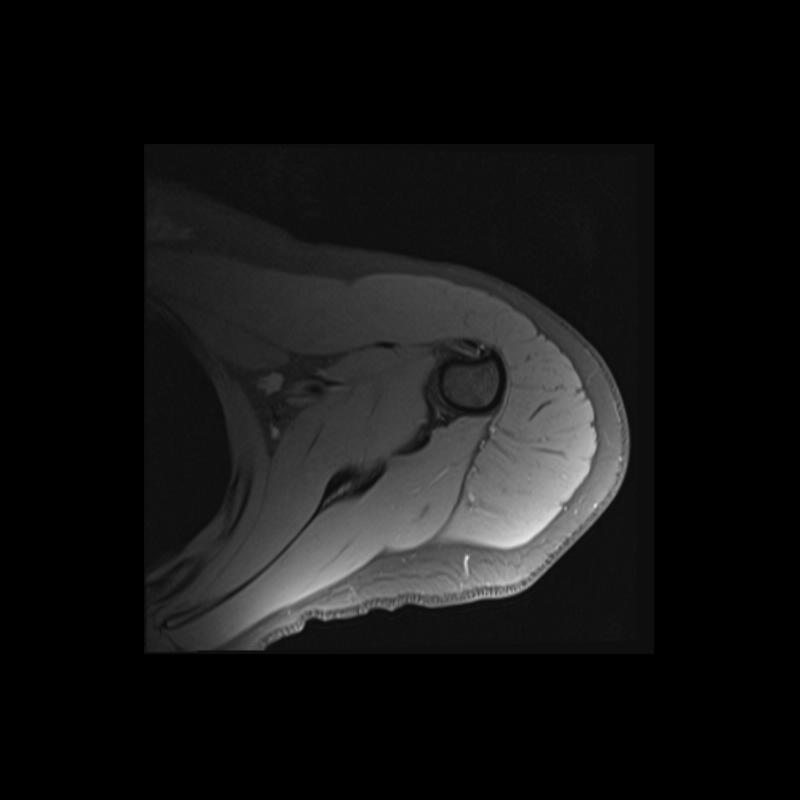

Shoulder MRI Anatomy